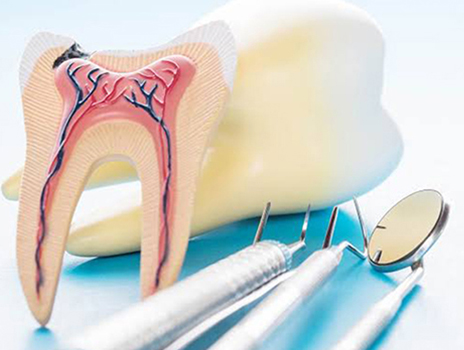

Root Canal Treatment

Root canal treatment is a procedure done when the tooth decay reaches the pulp causing pain & inflammation.

The procedure is

- Removal of infected tooth structure

- Clearing & Disinfection

- Filling with an inert material

- Restoration with crown or cap

Introduction

Root canal treatment is a common dental procedure that helps save an infected or damaged tooth. However, many people have questions and concerns about this treatment. In this blog post, we will provide answers to some of the most frequently asked questions about root canal treatment. By addressing these concerns, we aim to alleviate any fears or misconceptions you may have, helping you make informed decisions about your dental health.

What is a root canal treatment?

A root canal treatment, also known as endodontic therapy, is a dental procedure performed to save a tooth that has an infected or inflamed dental pulp. The dental pulp, which consists of nerves, blood vessels, and connective tissue, is located inside the tooth's root canals.

Why might I need a root canal?

You may require a root canal treatment if you have a severely decayed tooth, a deep dental cavity, a cracked or fractured tooth, or a dental abscess. These conditions can lead to pulp infection, causing pain, sensitivity, swelling, or even tooth loss if left untreated.

How is a root canal procedure performed?

The root canal procedure typically involves the following steps:

Is a root canal painful?

Contrary to popular belief, root canal treatments are performed under local anesthesia, ensuring that you won't experience any pain during the procedure. Modern techniques and advances in dentistry have made root canal treatments more comfortable and efficient than ever before.

How long does a root canal treatment take?

The duration of a root canal treatment varies depending on the complexity of the case and the tooth involved. In general, a root canal procedure can be completed in one or two appointments, lasting approximately 60 to 90 minutes each. Complex cases may require additional visits.

What should I expect after a root canal?

After a root canal treatment, you may experience temporary sensitivity or mild discomfort, which can be managed with over-the-counter pain relievers. It is essential to follow your dentist's instructions regarding oral care and attend any necessary follow-up appointments for optimal healing and restoration.

Are there any alternatives to a root canal?

In cases where a tooth is severely damaged or infected, a root canal treatment is often the best option to save the tooth. Extraction may be considered as an alternative, but it is generally recommended to preserve natural teeth whenever possible. Extracted teeth may require additional dental procedures, such as dental implants or bridges, to restore functionality and aesthetics.

How successful is a root canal treatment?

Root canal treatments have a high success rate, typically ranging from 85% to 97%. With proper oral care, including regular brushing, flossing, and dental check-ups, the treated tooth can last a lifetime.

Can a root canal treatment be performed on any tooth?

Root canal treatments can be performed on most teeth, including incisors, canines, premolars, and molars. However, in some cases, tooth extraction may be the only viable option if the tooth's structure is severely compromised.

Are there any risks or complications associated with root canal treatment?

As with any dental procedure, there are potential risks and complications associated with root canal treatment. These may include infection recurrence, fracture of the tooth, or damage to nearby structures. However, with proper technique and adherence to sterile protocols, the risk of complications is minimal.

How much does a root canal treatment cost?

The cost of a root canal treatment can vary depending on factors such as the tooth's location, complexity of the case, and whether a dental crown is needed for restoration. It is best to consult with your dentist, who can provide an accurate estimate based on your specific situation.

How can I find a skilled dentist for a root canal treatment?

To find a skilled dentist for a root canal treatment, consider the following:

Contact Sarvesh Dental Care - 9487758453 for further Information and Treatment.